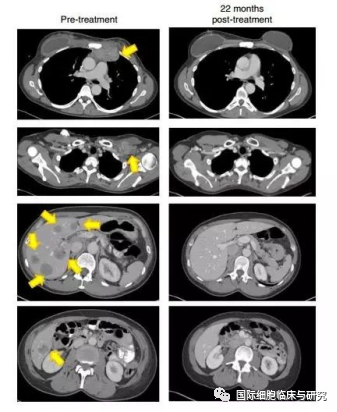

一名难治性激素阳性转移性乳腺癌患者接受了4种突变蛋白(SLC3A2,KIAA0368,CADPS2和CTSB)的TILs,治疗22个月后,患者肿瘤完全消失,且4年后仍未出现进展或复发。这一案例发表在2018年《自然医学》(Nature Medicine)杂志上。